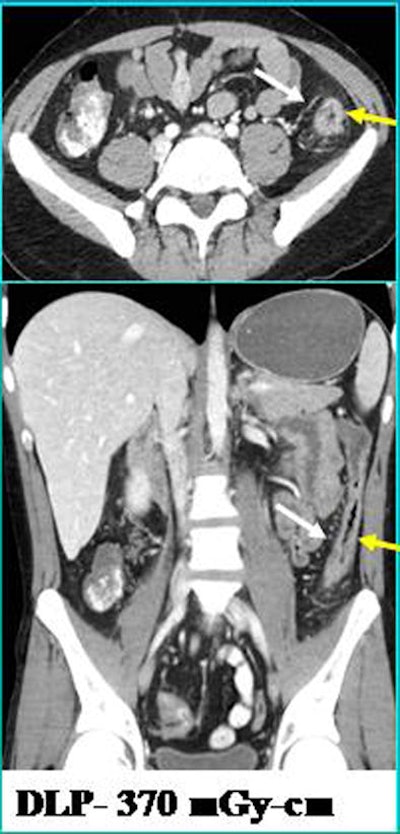

| FBP-enabled images acquired with a higher dose (above) are comparable to ASIR-enabled images (below). |